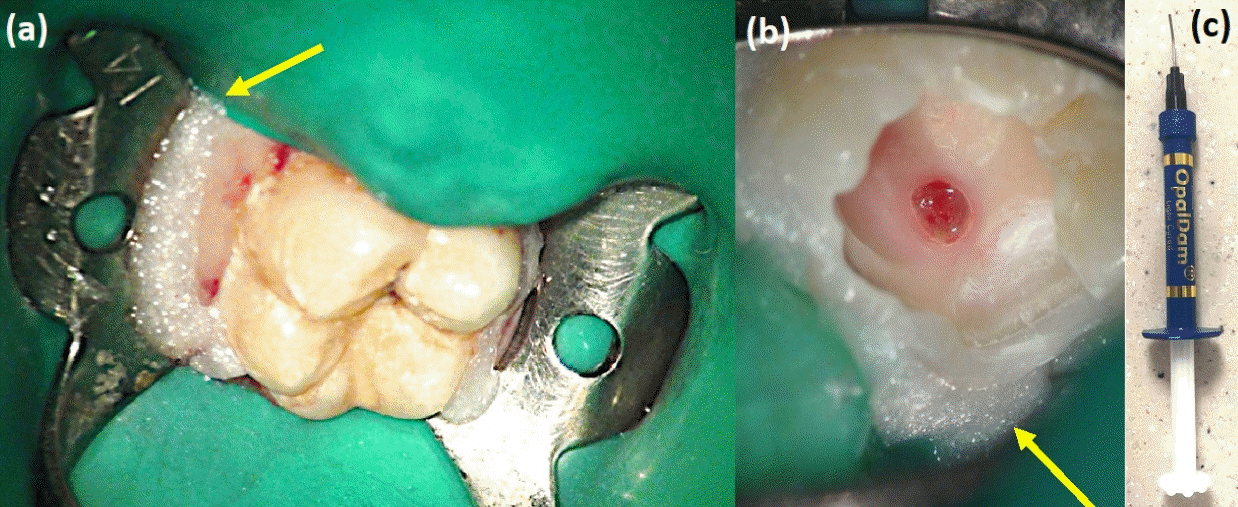

Figure 1.

A 14-year-old female patient underwent vital pulp therapy for occlusal and mesial caries on tooth #16. #26 (a) Unlike the occlusal caries, the mesial caries was relatively small. (b) After removing the mesial caries, a pinpoint pulp exposure, which was difficult to detect with the naked eye, was observed under high magnification of the microscope. There was no visible red bleeding, and it was hard to distinguish from the surrounding dentin. (c) Post-operative radiograph after direct pulp capping on the mesial side and partial pulpotomy on the occlusal surface.